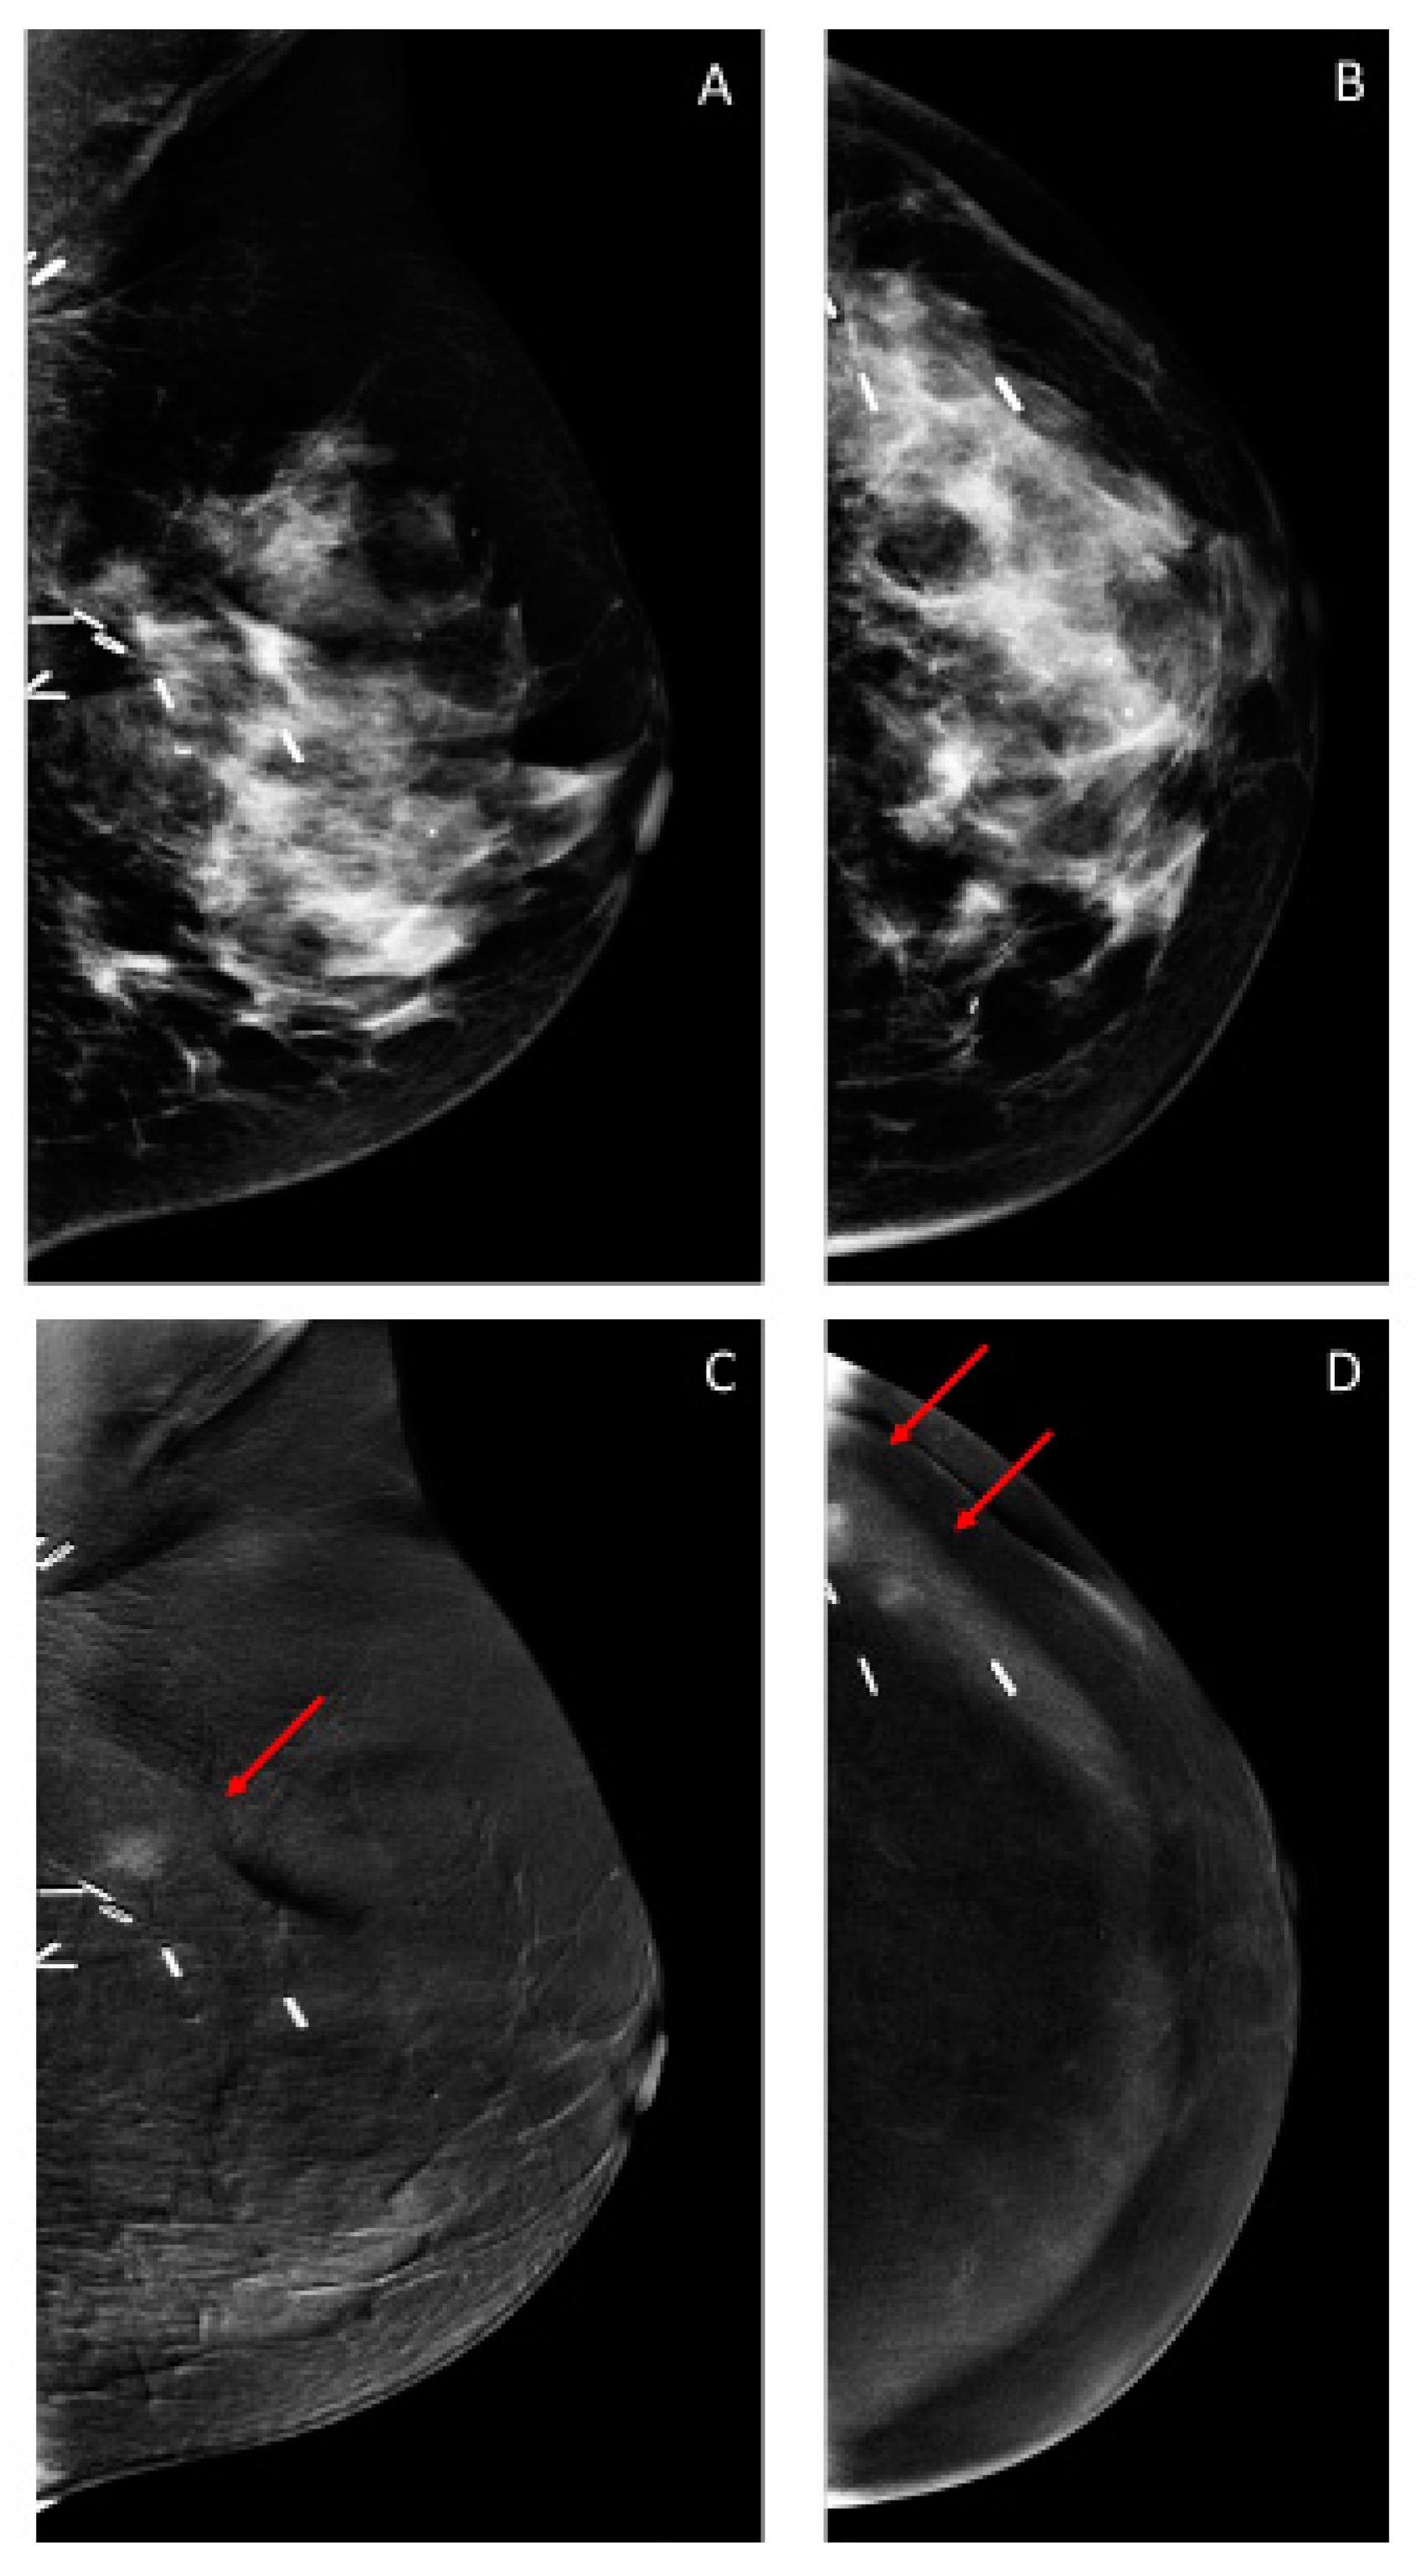

3.2. Findings on Low-Energy Images, With or Without Enhancement

3.3. Additional Findings on Iodine Images

3.4. Overall CEM Results